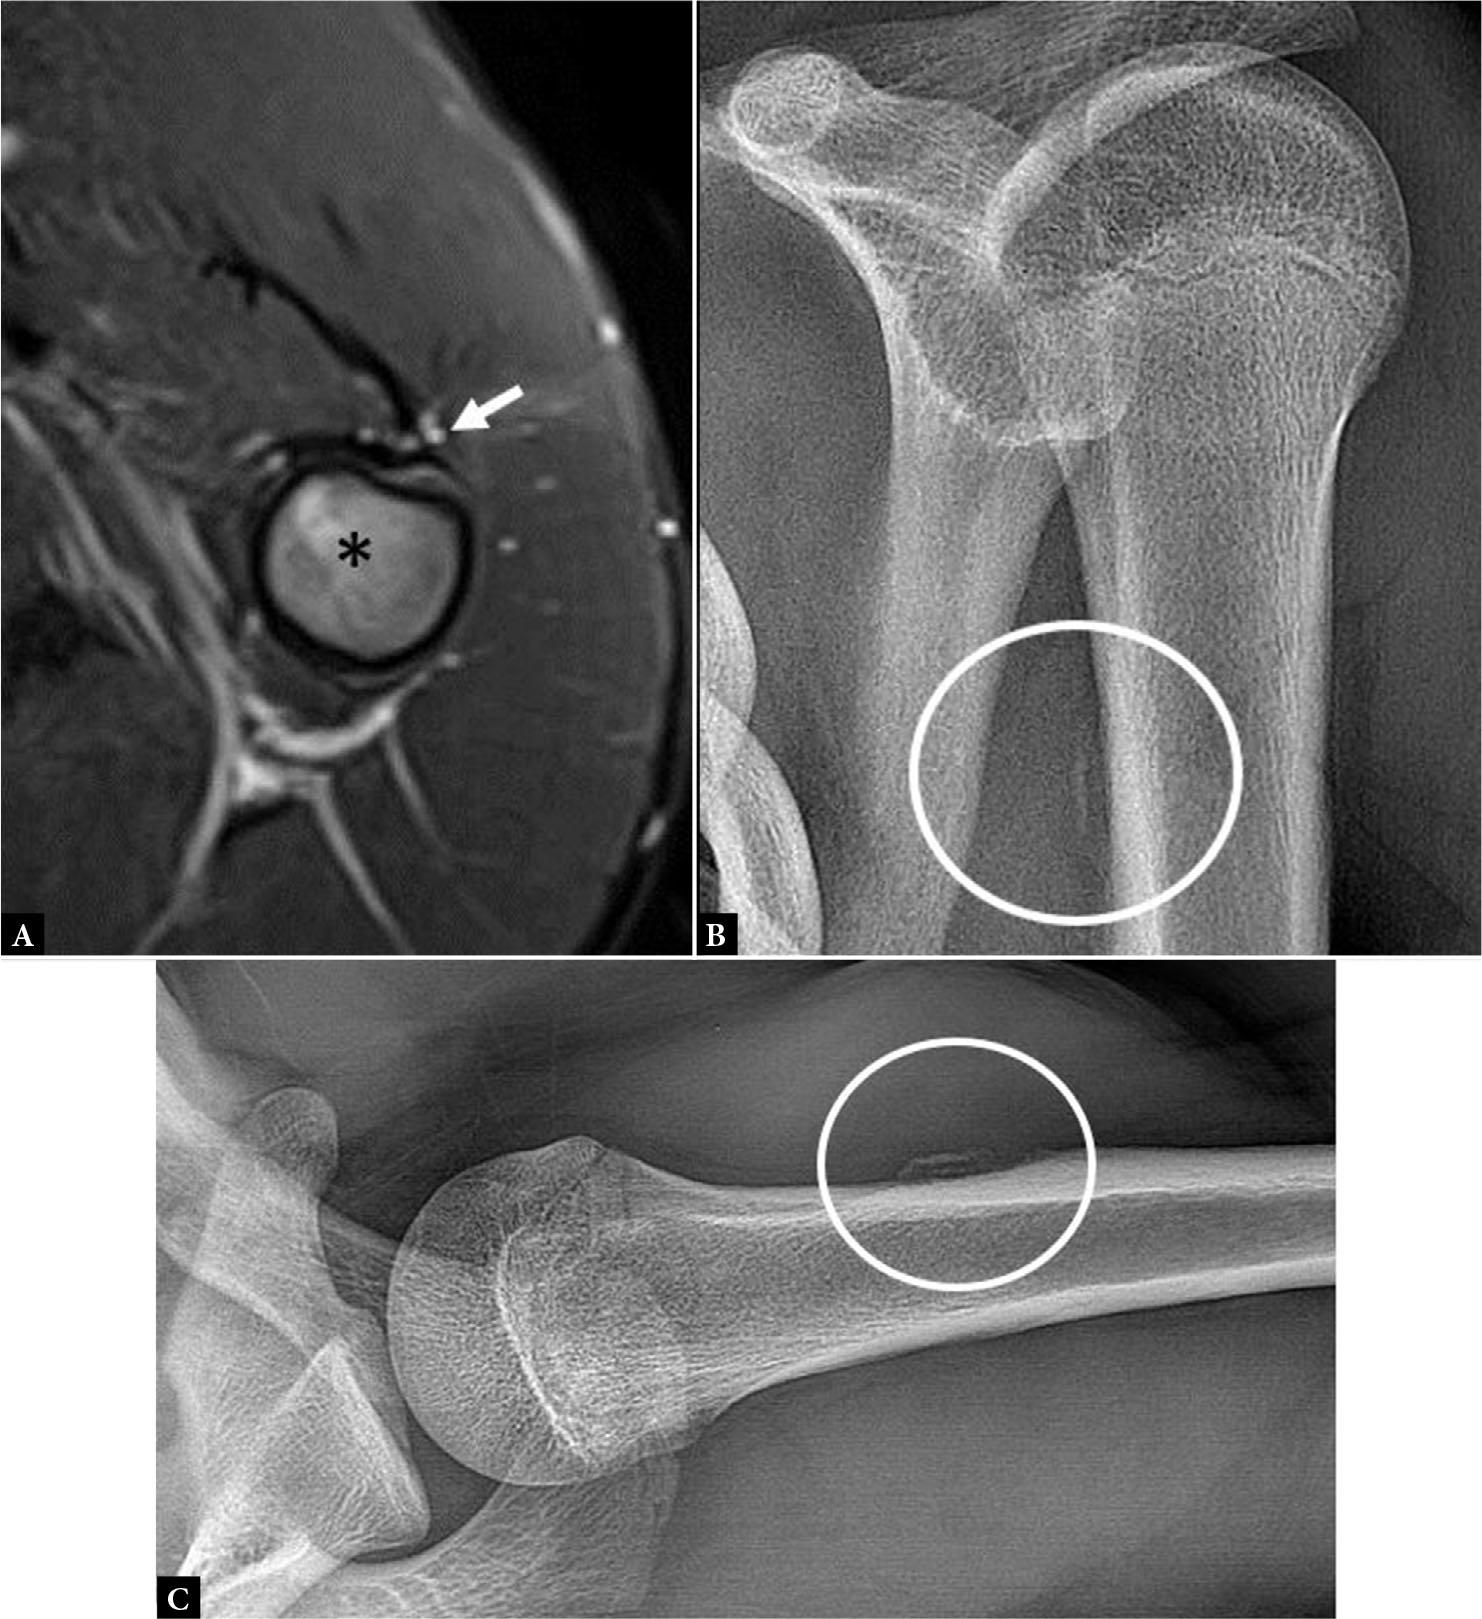

Fig. 12.

Axial fluid-sensitive MR image (A) shows avulsion of the PM tendon from the humeral insertion (arrow) with associated bone marrow edema (asterisk). AP (B) and axillary (C) radiographs of the shoulder show the avulsed cortical fragment from the anterior proximal humeral diaphysis (circle, B, C)